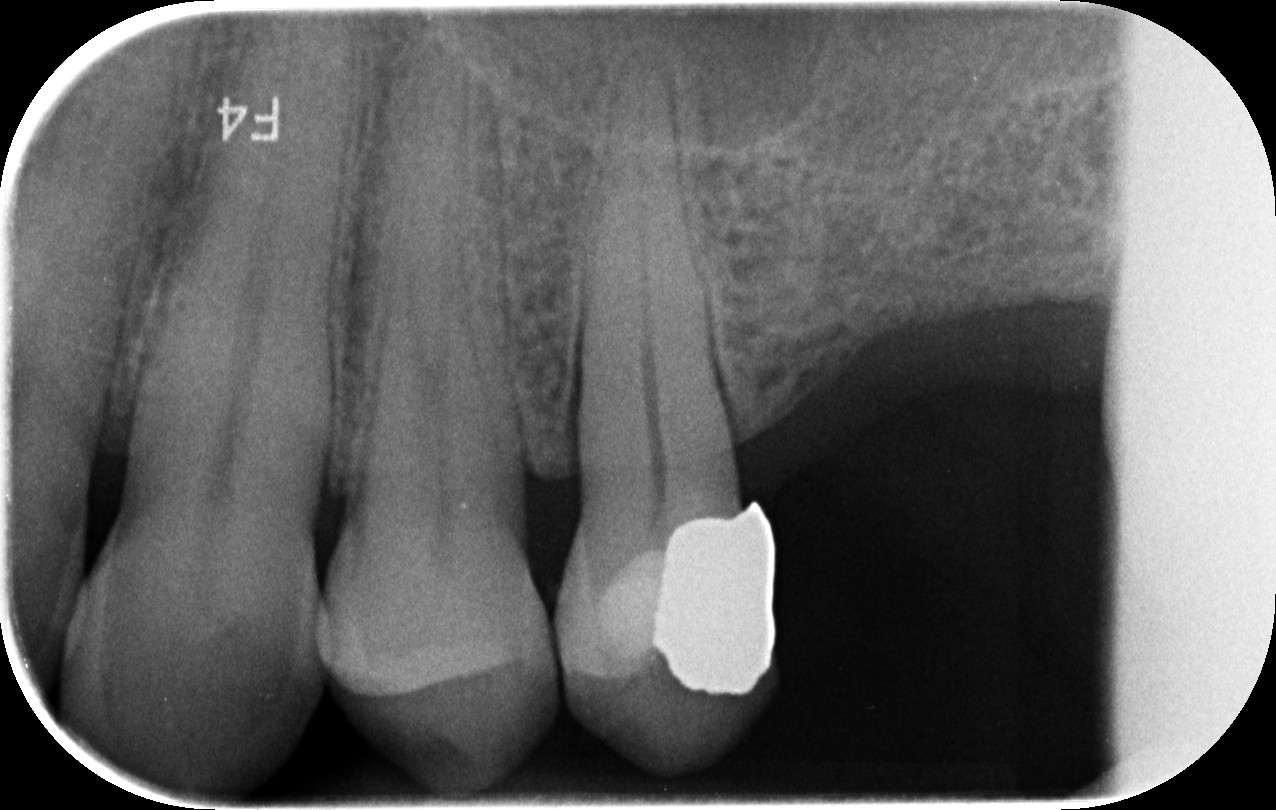

Původně se uvažovalo o ošetření pomocí korunky. V průběhu ošetření však pacientka zmínila klíčový detail – ulomený fragment zubu měla s sebou. Fragment přesně odpovídal místu lomu, což otevřelo možnost zcela jiného, neinvazivního řešení. Ulomený fragment byl nejprve dostatečně rehydratován ve fyziologickém roztoku.

Následně byl zub ošetřen adhezivní technikou a fragment byl přesně nalepen zpět na původní místo. Spojení bylo zpevněno moderními kompozitními materiály. Celý postup proběhl bez vrtání a bez chirurgického zákroku. Princip je obdobný jako při práci s výplní, rozdíl spočívá v tom, že se využívá vlastní zubní tkáň pacientky – což je z hlediska funkce i estetiky ideální řešení.

Bezprostředně po nalepení bylo při detailním zvětšení možné rozeznat místo spoje. Při kontrolním vyšetření po dvou týdnech už hranice lomu prakticky nebyla patrná. Zub drží, je plně funkční a působí přirozeně. Pacientka se vyhnula zákroku, který by pro ni vzhledem k biologické léčbě představoval zbytečné riziko.